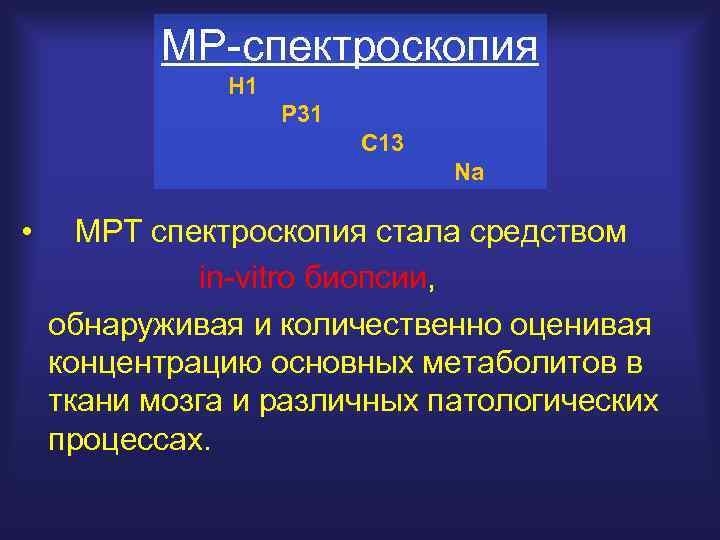

МР-спектроскопия H 1 P 31 C 13 Na • МРТ спектроскопия стала средством in-vitro биопсии, обнаруживая и количественно оценивая концентрацию основных метаболитов в ткани мозга и различных патологических процессах.